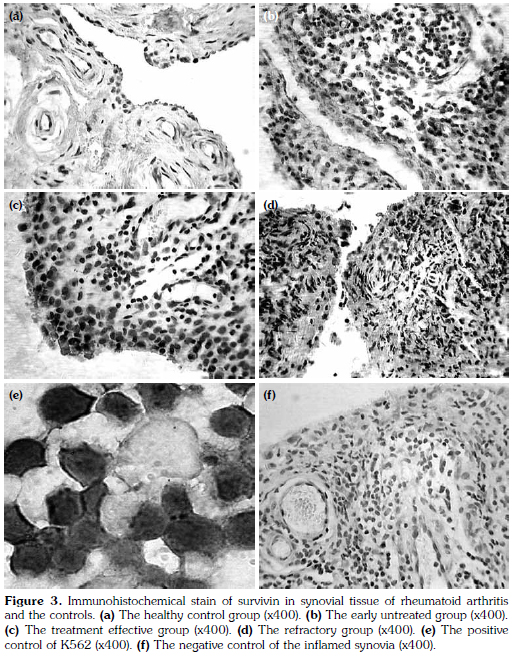

Fifty-one synovial tissues were obtained from 60 patients with RA and 20 patients of the control group and were stained by immunohistochemical staining methods. The positive cases of expression of survivin in synovial tissue from the early untreated group was significantly higher than in the controls (Chi-square=11.18, p=0.00) and the effective group (Chi-square=6.75, p=0.04). The positive cases of expression of survivin of the refractory group was significantly higher than the treatmenteffective group (Chi-square=7.10, p=0.03) and the controls (Chi-square=13.93, p=0.00). There was no significant difference between the refractory group and the early untreated group (Chi-square=0.31, p=0.86). Expression of survivin in synovial tissues from the four groups are shown in Figure 3a-d. The positive and negative controls are shown in Figure 3e, f. The positive cases of each group are shown in Table 4, 5.

Fifty-one synovium samples were obtained from the 60 RA patients and the trauma joints of the 20 healthy control group, following joint replacement surgery or synovectomy. Specimens were fixed in 10% neutral-buffered formalin (pH 7.4) at 4 °C for 24 hours and embedded in paraffin. Four-micrometer thick tissue sections were used and dewaxed in xylene and rehydrated through decreasing concentrations of ethanol and water. Immunohistochemical staining for survivin expression was carried out using a standard immunoperoxidase technique (ABC-method). All slides were warmed up for 35 min to a temperature of 55 °C for dewaxing, boiled in 10 mM citrate buffer (pH 6.0) by microwave treatment (600 W) for 20 min for demasking the antigens. All stainings were performed in cover slides in combination with the prepared slides; K562 cells as positive control and one negative control were included. Once the slides with endogenous peroxidase was immersed in methanol with 0.03% hydrogen peroxide for 12 min, endogenous peroxidase activity was blocked. The primary antibody was incubated for 30 min at a temperature of 37 °C (dilution 1:200, GTX100052, USA). After washing with PBS-buffer, the secondary antibody was applied at room temperature for 12 min. The staining for survivin was visualized with the DAB kit (Beijing Zhong shan Golden Bridge Biotechnology Co., Ltd). The specimens were counterstained with hemalum. The stained specimens were viewed at an objective magnification of x200 and x400 by three investigators.

Cells stained brown were considered positive. With 50 cells per field, at least four fields were randomly observed under high magnification. The percentage of positive cells in total cells were calculated. Staining results were divided into: (i) negative (-), no significant difference between cell color and the background. (ii) Weakly positive (+), positive cells <10%. (iii) Positive (++), positive cells account for 10% ~50%. (iv) Strongly positive (+++), positive cells >50%.